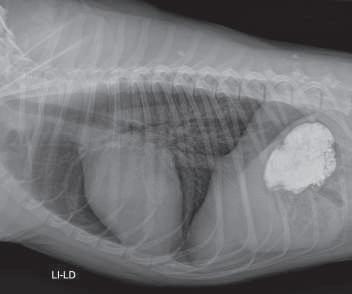

Estudio radiográfico con medio de contraste positivo (sulfato de bario), Li- Ld. Se observa que el medio de contraste pasó en su totalidad al estómago. (p.

Hernia hiatal en un perro, tratada únicamente con gastropexia: Informe de un caso.

Paulina María Carrillo-Solís, Hortensia Corona-Monjarás, Octavio Mejía-Ponce

Hiatal hernia treated in a dog solely with gastropey: a case report. .

tivo, en un intento de diferenciar vómito de regurgitación, se realiza estudio radiográficosimple(sincambiosradiográficos aparentes) (Figuras 1 y 2) yconmediode contraste (sulfato de bario) (Figura 3); se encuentra un tránsito normal del esófago y del estómago.